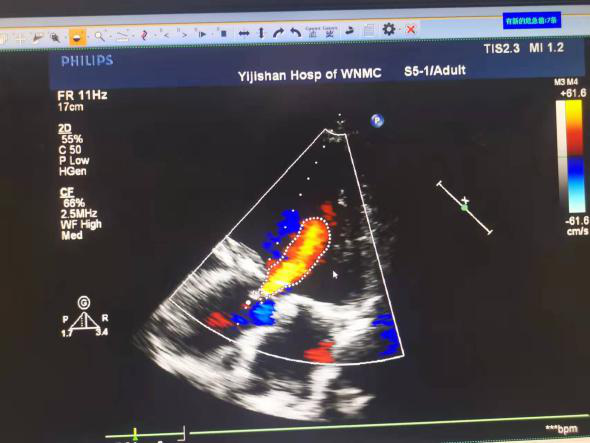

近日,皖南医学院弋矶山医院心脏大血管外科张大发教授团队,运用VitaFlow Liberty™经导管主动脉瓣膜系统成功为一例主动脉瓣重度反流、二尖瓣、三尖瓣中度反流,左心显著增大,瓣环、流出道极限值且极低EF的患者成功实施了TAVR手术。

半年来偶感胸闷,心慌,近一个月来因肺部感染导致胸闷心慌加重,就诊于当地医院;超声心动图示:升主动脉硬化并扩张,重度主动脉反流,左心明显增大,中度二尖瓣反流,中度肺动脉高压伴中度三尖瓣反流,左室收缩功能减退,EF值30%。当地医院建议转院进一步诊治,遂至皖南医学院弋矶山医院就诊,诊断为主动脉瓣重度关闭不全,二尖瓣中度关闭不全,心功能IV级。

释放后造影,无瓣周漏